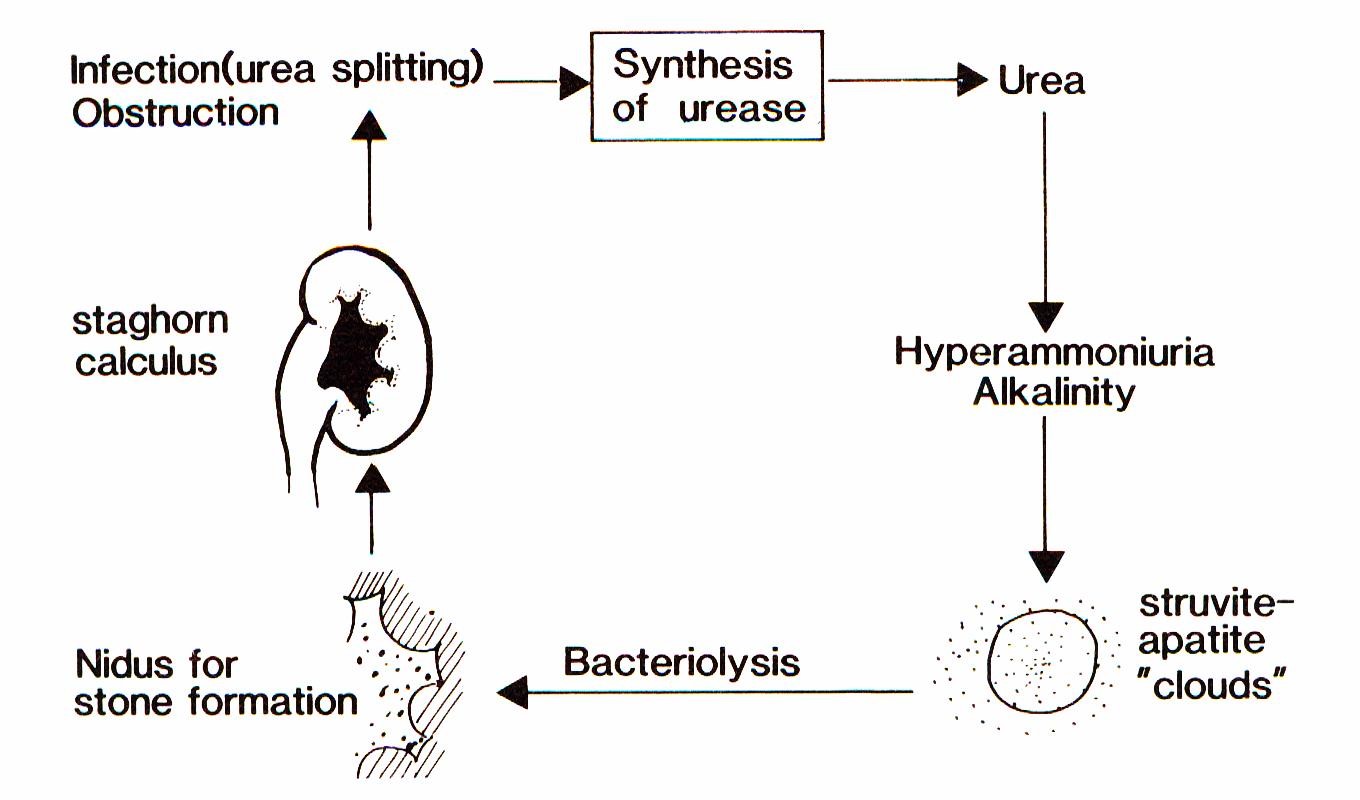

The term “infection induced urinary stones (IIS)”, however, means that there is not only an association of stones and urinary tract infections (UTI) but a causal relationship. Already more than a hundred years ago, T.R. Brown [3] reported that some bacteria caused the formation of urinary stones consisting of calcium and magnesium phosphate. Sumner [4] isolated the bacterial enzyme urease which splits urea into ammonium and carbonate ions resulting in supersaturation and alkalization of the urine. Struvite and apatite clouds develop in which crystal growth is supported. These crystals deposit on the surface of the bacteria. Within the bacteria mainly carbonate apatite crystals form. After lysis of the bacteria, these crystals serve as new germs for stone formation (Figure 1) [5].

The pathogenesis of struvite, which is the most frequent IIS, has been outlined already above (see Introduction).